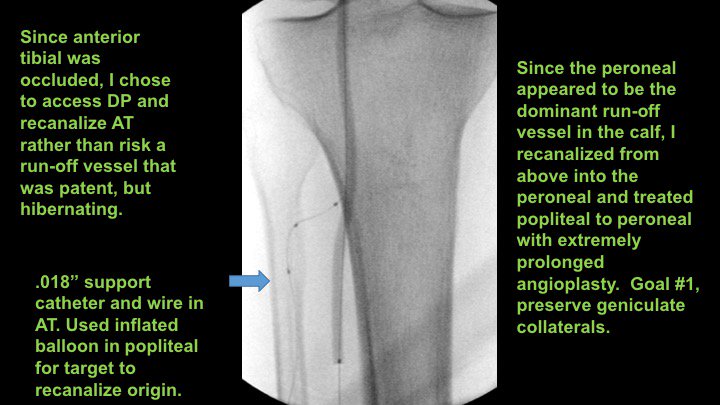

MRA can be MORE sensitive to tibial occlusive disease than DSA. MRA helped plan approach due to knowledge of hibernating AT and peroneal lumen. Successful antegrade luminal recan for #CLI #CLIfighters #mylegmylife @FadiSaab17 @Mustapja @roblookstein @DrBTKatzen @BOlivieriMD